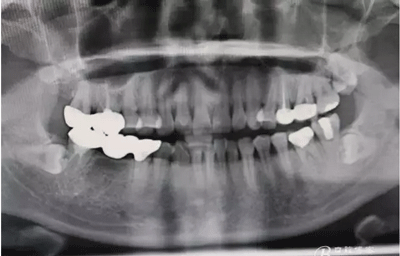

圖1.下頜47-45全瓷橋修復(fù),17、16全瓷連冠修復(fù)。48低位水平阻生。